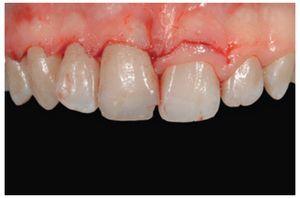

Tras una limpieza exhaustiva y una sesión de motivación sobre higiene oral (figura 34), el plan de tratamiento prosiguió con una limpieza cavitaria minuciosa para eliminar la por caries. Los márgenes fueron pulidos para eliminar las zonas que pudieran retener placa bacteriana y se realizó un retratamiento de conductos.

Figura 34 Vista del grupo incisivo tras fase de higiene oral, motivación de la paciente y limpieza de las restauraciones provisionales.